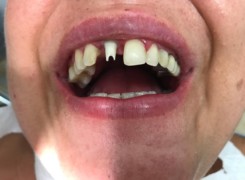

Pan Kamil zgłosił się do gabinetu po wypadku rowerowym w wyniku którego wybił ząb – lewą górną jedynkę. W takiej sytuacji została podjęta decyzja o implantacji natychmiastowej oraz zapatrzeniu pacjenta na czas integracji wszczepu w uzupełnienie tymczasowe.

Poniżej przebieg odbudowy protetycznej.